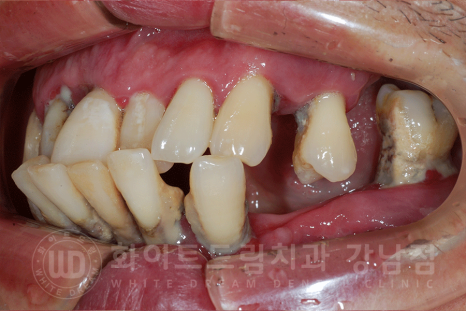

오늘 내원하신 환자분은 치과를 오랜 기간 오지 못하시고 잇몸 약만 오랜 기간 복용을 하신 분인데요.

구강 사진을 보면, 구강 내 치석이 많이 위치하고 있는 것이 보입니다.

초기 치석은 눈에 보이는 잇몸 위쪽으로 자리를 잡다 점점 잇몸 안쪽 즉, 치아 뿌리 부근까지 번지게 됩니다.

그럼, 치석으로 인해 생긴 염증이 잇몸뼈를 녹이기 때문에 치주염이 심하면 이렇게 앞니가 전방으로 돌출되게 됩니다.

잇몸뼈가 치아를 단단하게 잡아줄 수 없기 때문이죠.

환자분의 x-ray를 보면 대다수의 치아가 없는 상태이고,

그나마 남아있는 치아들도 쓰러져있거나 치아 뿌리만 잇몸뼈에 겨우 매달려있는 상태였습니다.

치주염이 굉장히 심한 상태여서 살릴 수 있는 치아는 없었기에

전악 발치 후 전체 임플란트 치료를 진행하기로 했습니다.